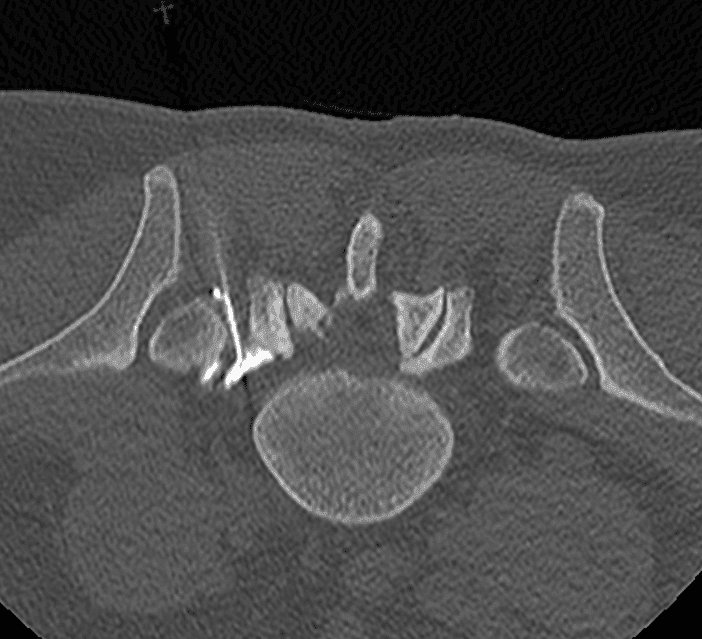

Scanner

Une imagerie (scanner ou IRM) est réalisée en amont pour établir le diagnostic, évaluer l’anatomie discale et planifier la trajectoire d’insertion.

Le guidage en temps réel par fluoroscopie ou scanner assure une précision optimale, minimisant ainsi le risque de lésion des structures adjacentes.

Résection du noyau pulpeux

Une fois l’aiguille en place, des instruments spécialisés (curettes ou dispositifs aspiratifs) sont utilisés pour retirer une portion du noyau pulpeux.

Contrôle final

Un contrôle imagerie est effectué en fin d’intervention pour vérifier la qualité de la décompression et la bonne répartition des espaces discaux, garantissant ainsi l’efficacité du geste.